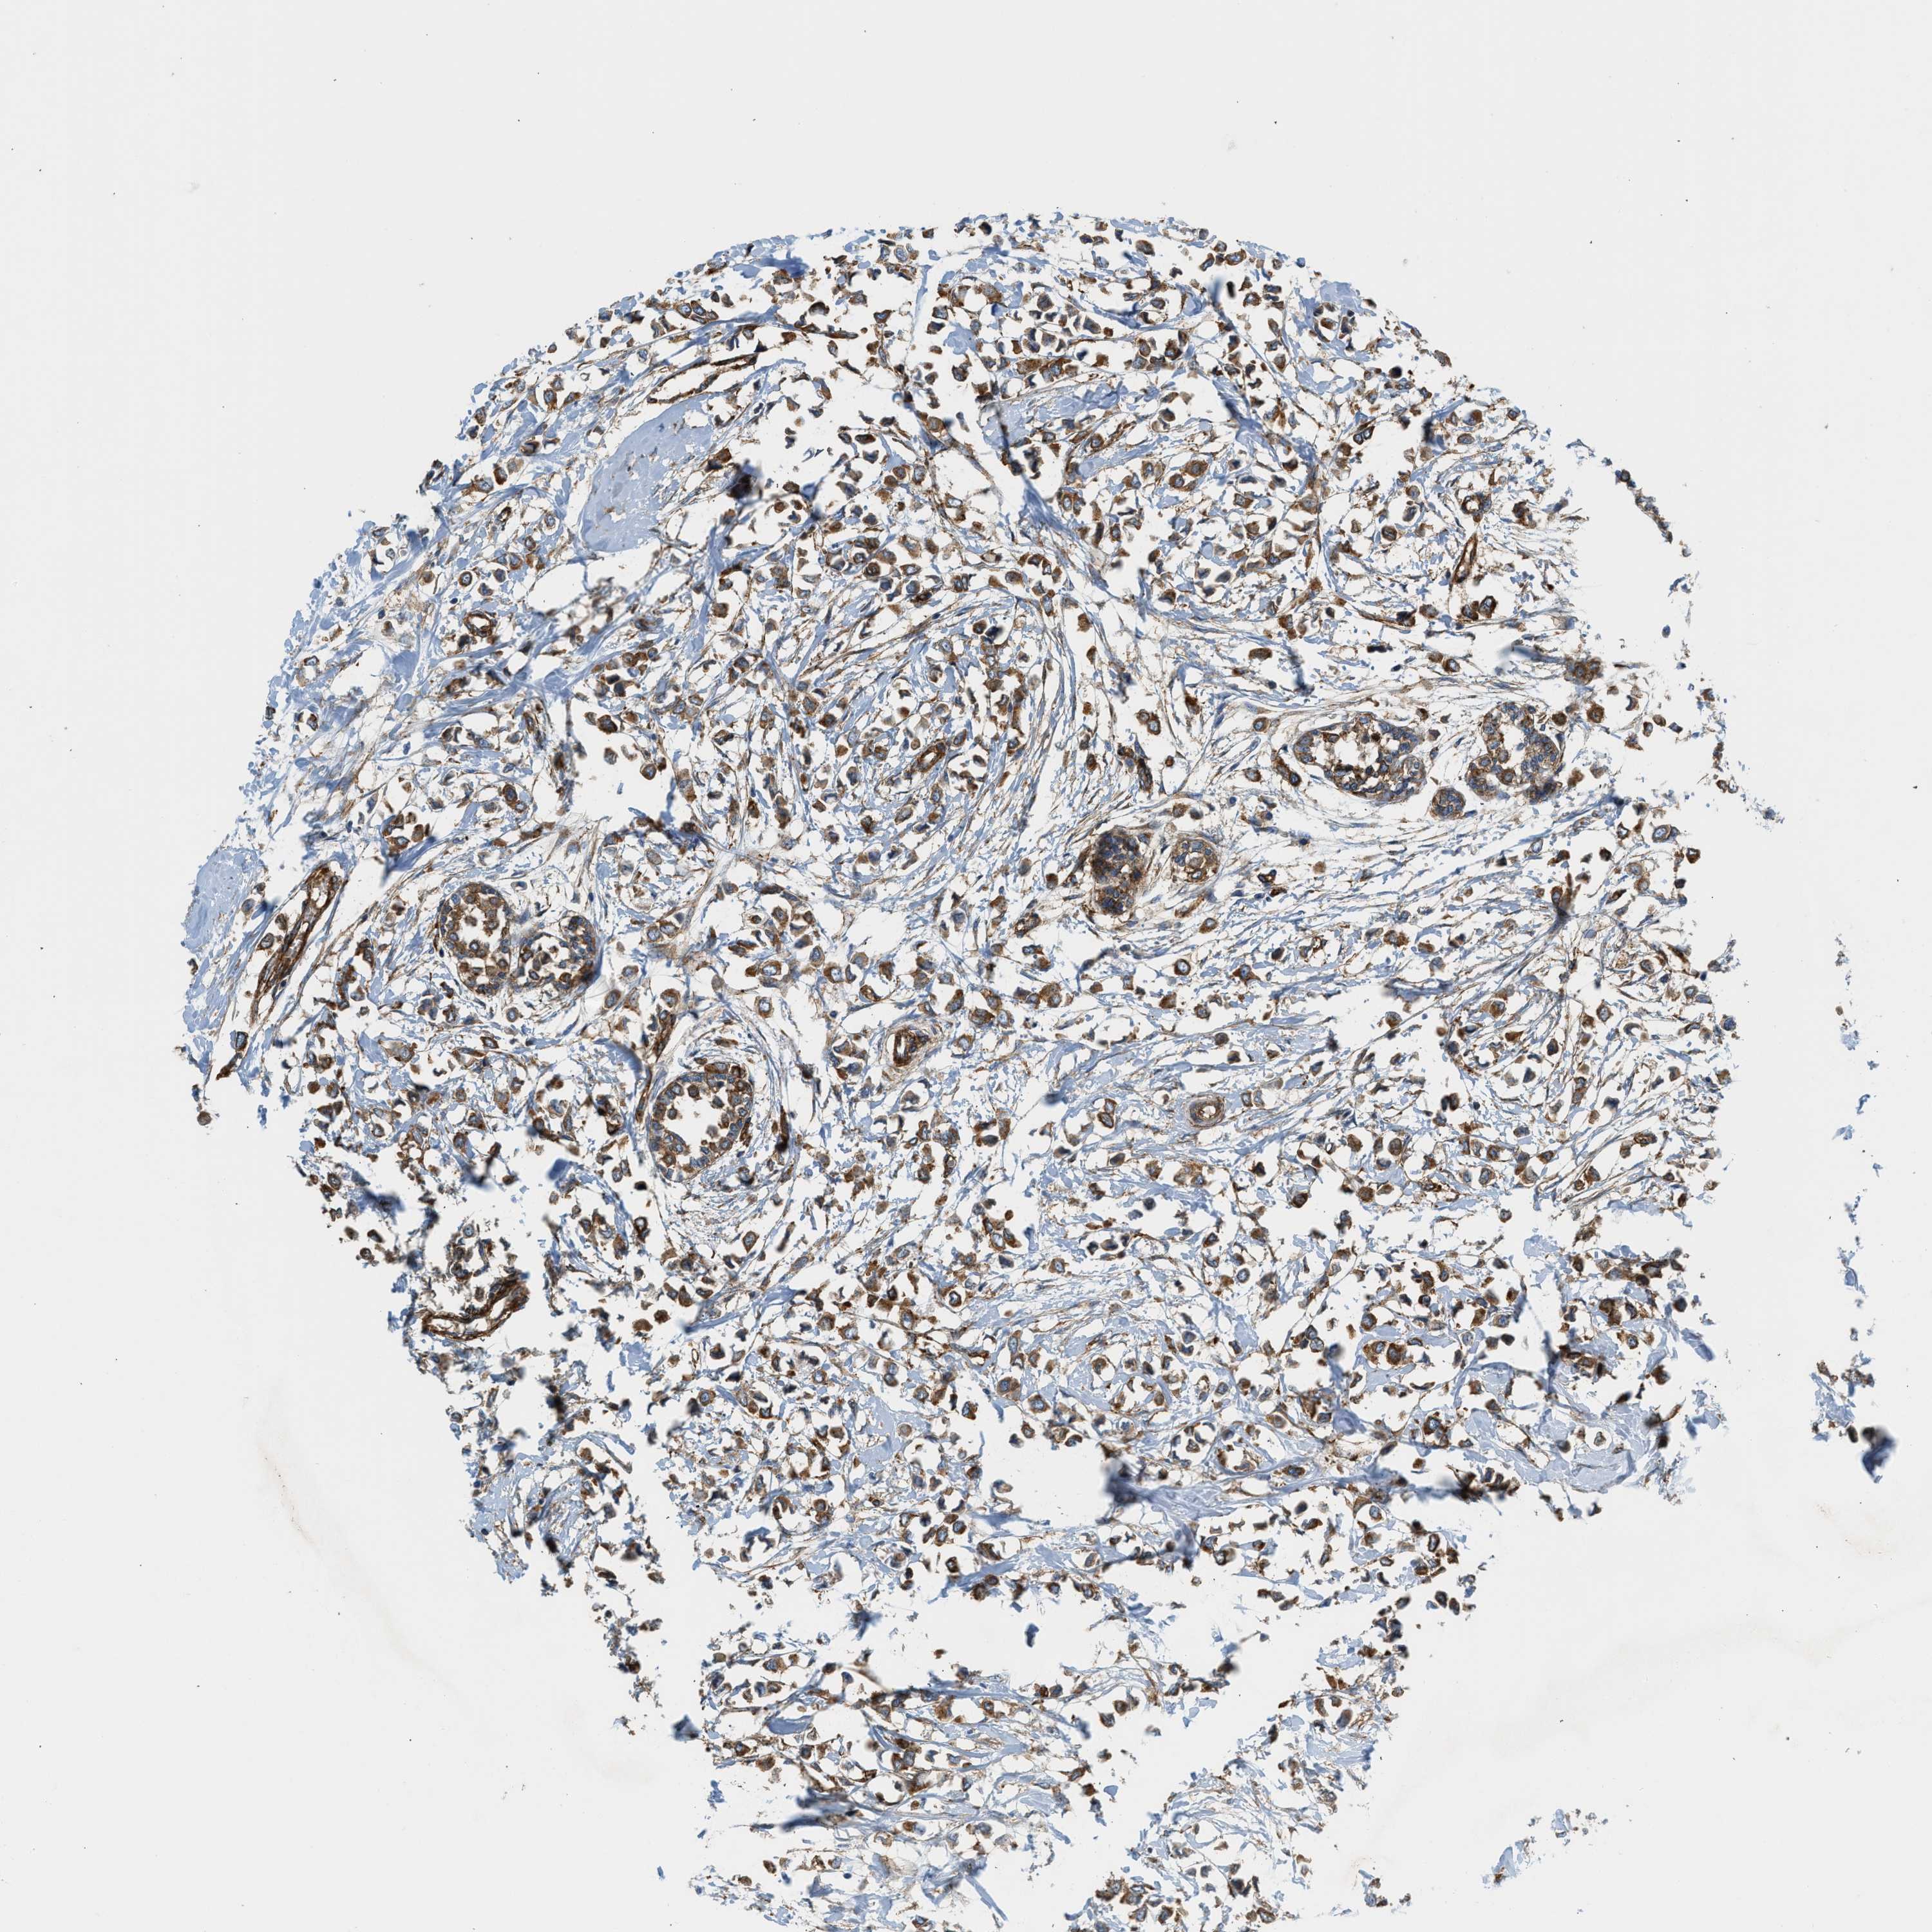

CANCER BREAST CANCER Show tissue menu

BRCA TCGA BRCA VALIDATION PROTEIN EXPRESSION

Breast cancer

Human cancer